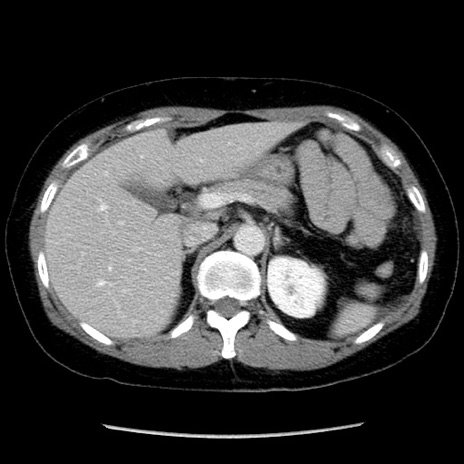

矢状断像